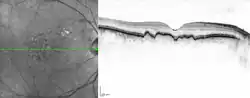

| Macular soft drusen in the right eye of a 70-year-old male. | |